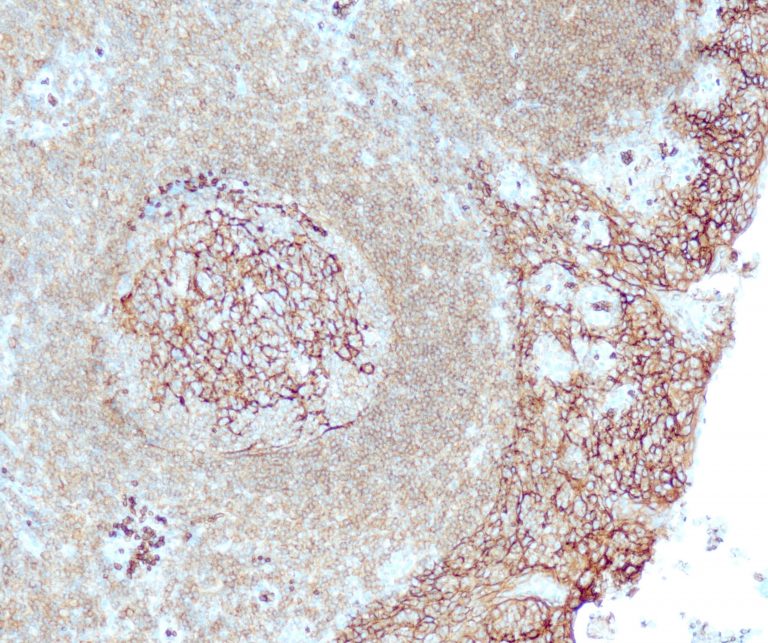

General Marker